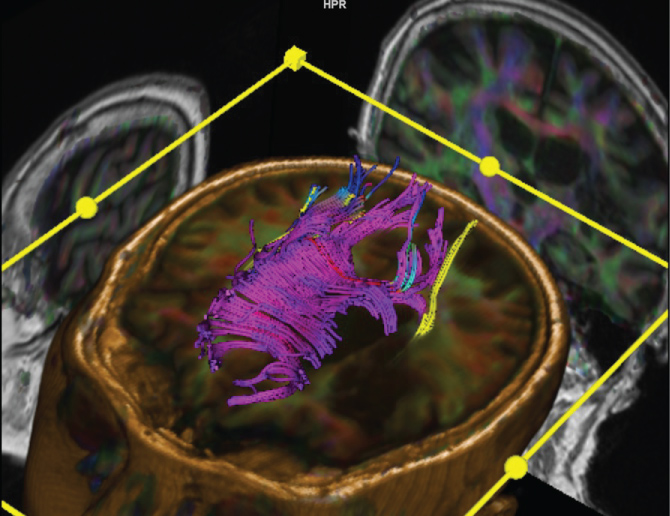

Three subjects were excluded after the full initial scan due to poor imaging quality (movement artifacts or inability to complete the imaging protocol). Seven subjects were included and were studied before and after the injections. The obtained images were post processed in an independent workstation using Syngo Via® software to image the corticospinal tracts of the affected and contralateral sides (Figure 1 and Figure 2), the corpus callosum (Figure 3) and the tracts in the white matter of the frontal, parietal, temporal and occipital lobes of the affected and contralateral sides. The seeding points for tractography [21] were placed in the rostral cerebral peduncles on axial plane for the corticospinal tracts, in the corpus callosum on the sagittal plane, and in the white matter of the cerebral lobes within the boundaries set by the Talairach Atlas on axial plane. Fractional anisotropy values were obtained for each of the tracts. Each measurement was repeated three times to ensure consistency.

Figure 2: DTI fused to 3D T1 showing CSTs (yellow and blue) and CC (purple). View Figure 2